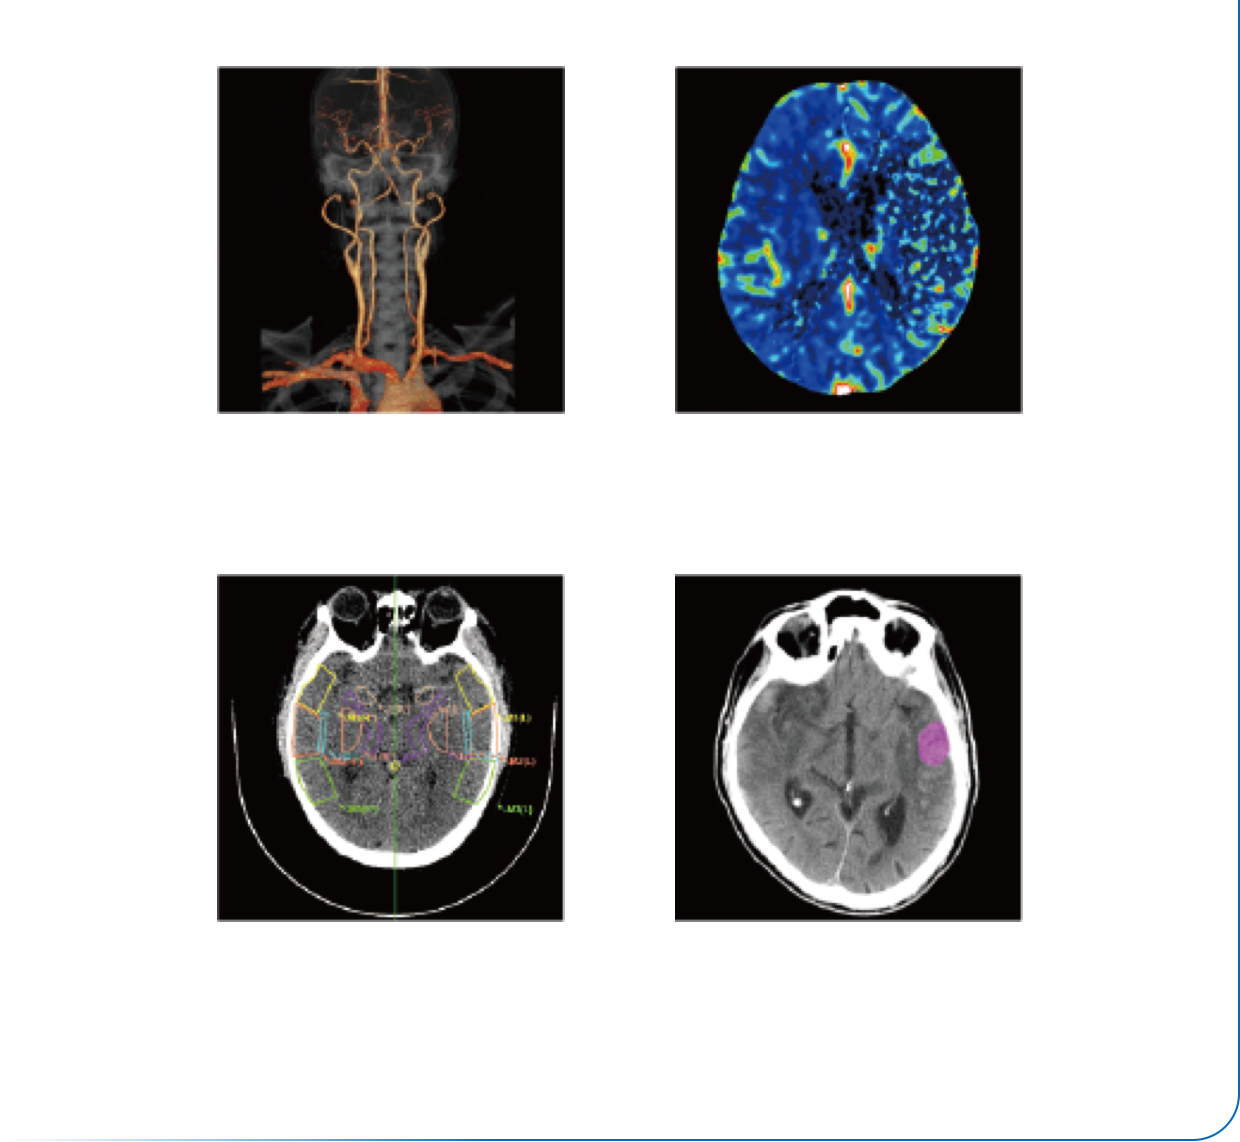

澎湃动力超强扫描

智能工作流*

个性化扫描协议

智能扫描范围

低kV成像技术

智能全域迭代iDream

智能剂量预警

智能剂量报告